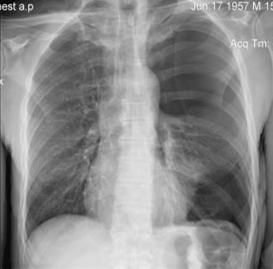

Rx toracică, incidență P-A

DESCRIERE:

DX: emfizem pulmonar

DD: